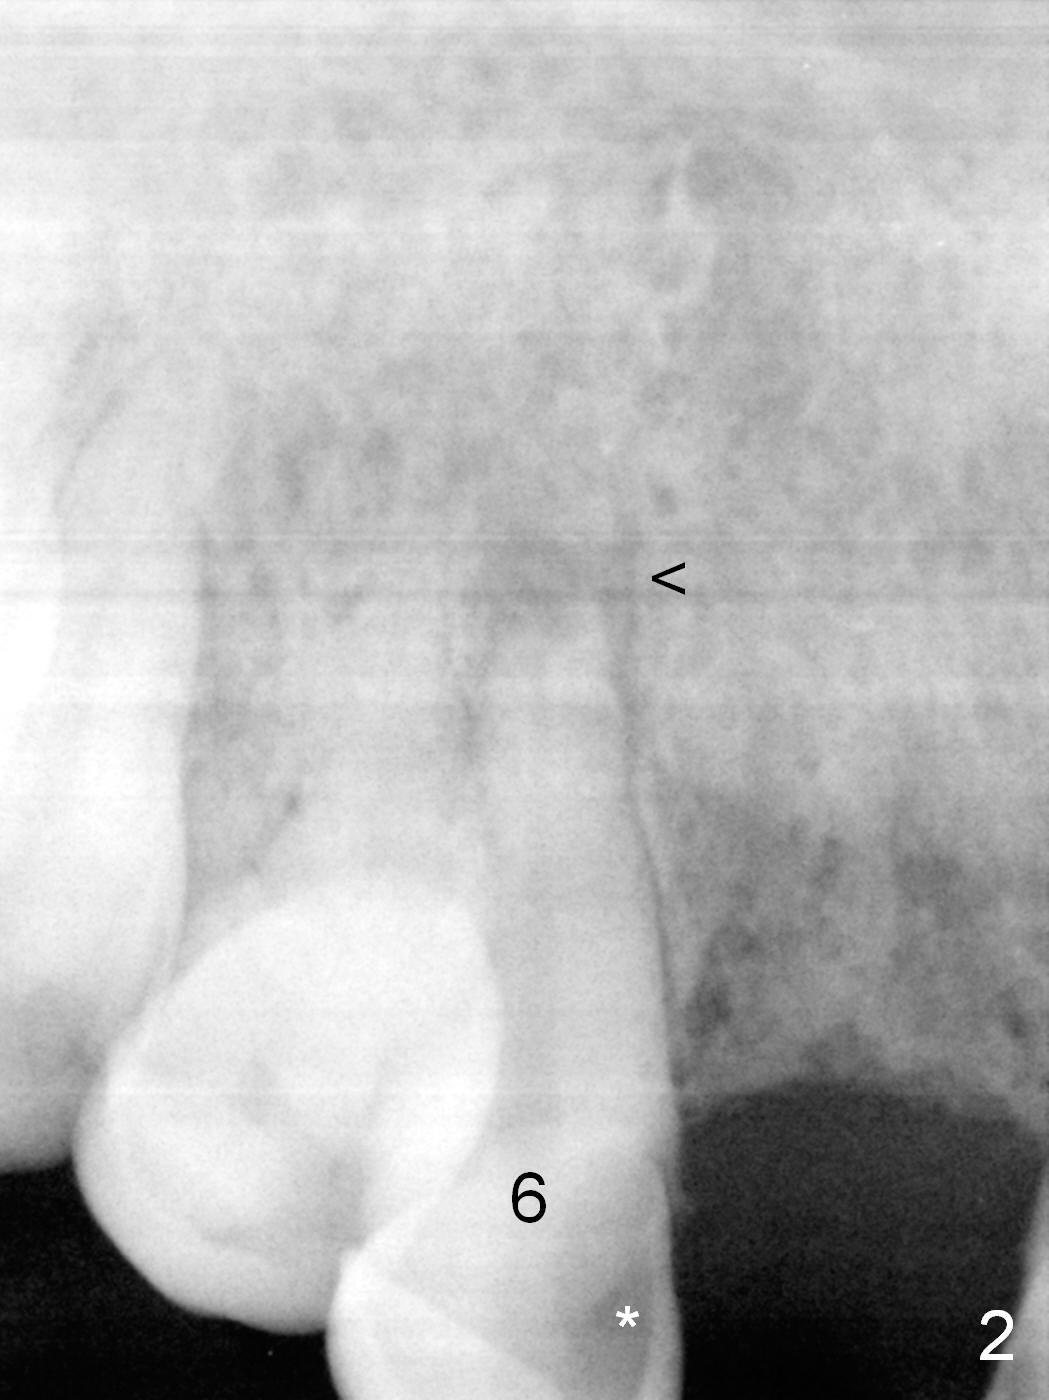

Implant placement at #31 reveals that bone width (bucco-lingual) is not a problem for a 64-year-old man. He requests implant placement at #7 and 14 (Fig.1,3), because the upper flipper has been lost. He wants to make sure that the implant at #7 does not cause the pain at #6. In fact the flipper appears to have lead to caries (Fig.2 *) and periapical radiolucency (<) at #6. RCT is rendered at #6 prior to a 1-piece implant at #7 (Fig.1). Since bone height is sufficient, the implants do not have to penetrate the nasal floor (Fig.1 v) or the sinus floor (Fig.3 <) unless the bone density is low. Prepare implant positioner of 4 mm to determine whether the ridge is wide to hold a 3.8 or 4 mm implant. Take preop photos to show the ridge width.